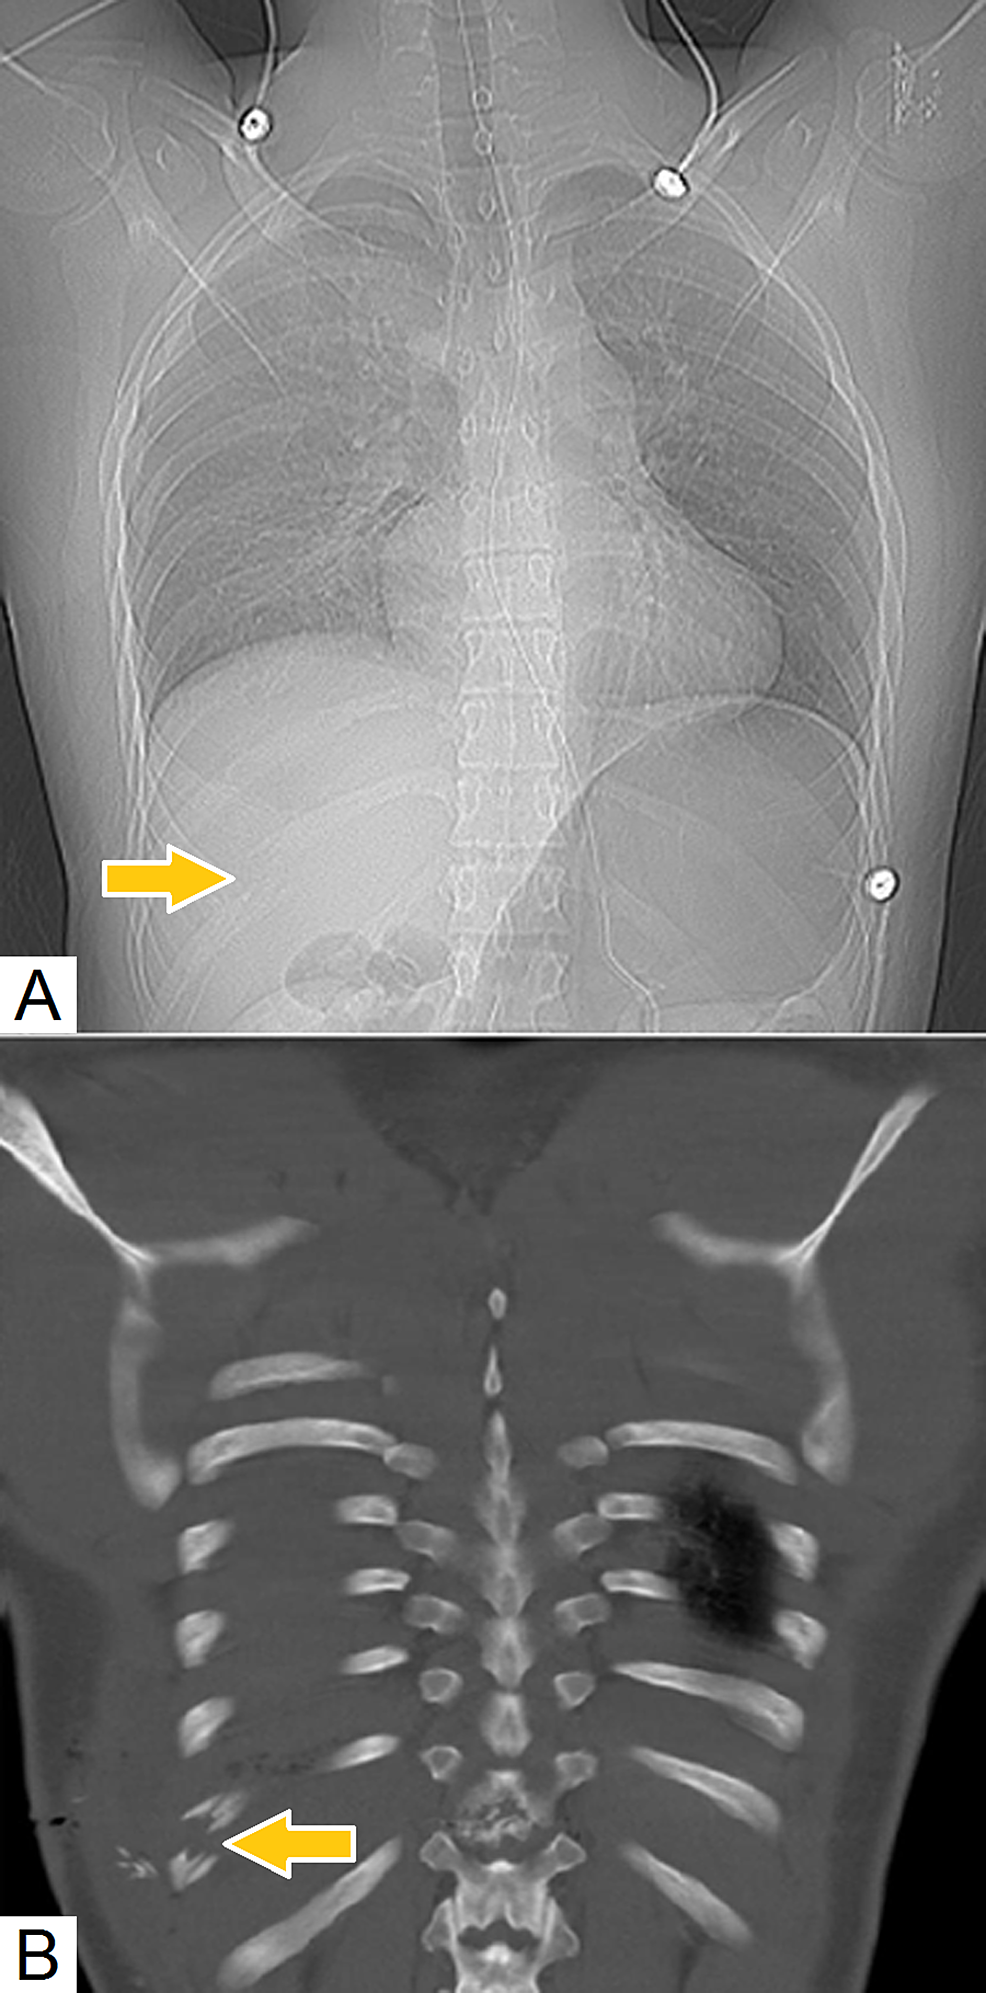

from pediatricimaging.org

Pediatric Rib Fracture Pediatric Radiology Reference Article

Pediatric Rib Fracture Pediatric Radiology Reference Article Rib Fracture Delivery A rib fracture is when one of more of the bones in your rib cage breaks or cracks. Rib fractures can be relatively benign, but often may be a marker of concomitant injuries such as pneumothorax,. • a fall • a. It is designed to optimise early acute pain management and. A rib fracture is when one or more of. Rib Fracture Delivery.

Pediatric Rib Fracture Pediatric Radiology Reference Article Rib Fracture Delivery What is a rib fracture? A rib fracture is when one or more of the bones in your rib cage breaks or cracks. Rib fractures and chest injury. This is usually caused by: This leaflet is about the injury to your chest wall, including: This guideline for use in all patients presenting with multiple rib fractures. • a fall •. Rib Fracture Delivery.

Pediatric Rib Fracture Pediatric Radiology Reference Article Rib Fracture Delivery It is one of the most common chest injuries and can result. Rib fractures can be relatively benign, but often may be a marker of concomitant injuries such as pneumothorax,. The following flow chart is intended to guide initial investigation, treatment, and clinical risk stratification for patients with chest wall. A rib fracture is when one or more of the. Rib Fracture Delivery.

Pediatric Rib Fracture Pediatric Radiology Reference Article Rib Fracture Delivery This guideline for use in all patients presenting with multiple rib fractures. A rib fracture is when one or more of the bones in your rib cage breaks or cracks. This leaflet is about the injury to your chest wall, including: Rib fractures can be relatively benign, but often may be a marker of concomitant injuries such as pneumothorax,. The. Rib Fracture Delivery.